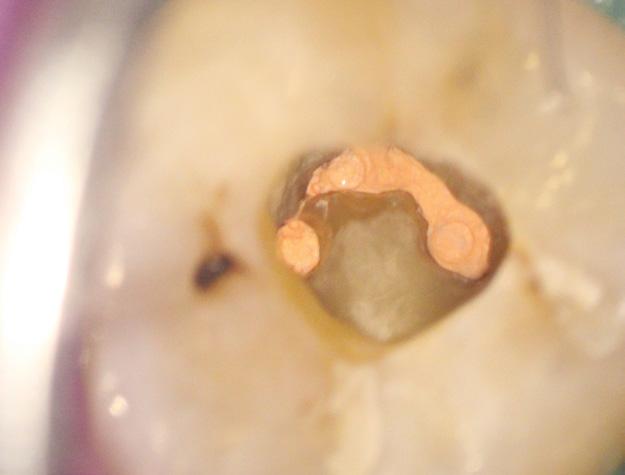

Intra-oral photograph of lesion A 75-year-old male was urgently referred to me by his dentist for assessment of a large, painless mass extending across the left maxillary alveolus. The patient had recently had a fall, and attended for a new partial denture, and he noted that it no longer fit. He was otherwise unaware of the mass. Given the presentation, the dentist made phone contact to emphasise the urgency of the patient’s triaging.

His medical history was significant for cardiovascular disease; cardiac arrhythmia, hypertension and hypercholesterolaemia. He had a pacemaker in-situ and was taking Amiodarone hydrochloride (antiarrhythmic) Bisoprolol fumarate (beta blocker), Rosuvastatin (HMG-CoA inhibitor), Aspirin and Eliquis (antithrombotic agents). He had a history of adenocarcinoma of the colon in 2005 treated with chemotherapy. He denied any other intervention for this malignancy and despite best efforts no other details were obtained. Clinical examination revealed a frail looking gentleman, without any obvious sign of ataxia or cachexia. Lymphadenopathy was not obvious on extraoral examination. Intraoral examination showed a mass measuring approximately 50mm in an anterior-posterior direction and 30mm transversely. The mass was erythematous and ulcerated, and the teeth involved demonstrated marked mobility.

Multiple incisional biopsies were completed across the lesion and the patient was sent for imaging; a CT extending from the diaphragm to floor of orbit.

In this case potential diagnosis is:

Hyperplastic tissue; due to an old and ill-fitting denture Angiogranuloma; reactive inflammatory response Squamous cell carcinoma; most common oral malignancy Oral melanoma; rare oral malignancy Metastatic adenocarcinoma; rare intraoral metastasis of his primary malignancy

Know the answer?

Turn to page 38 to see if you're right.

Clinical ChallengesAnswer in Oral Medicine

The correct diagnosis was:

Oral melanoma; rare oral malignancy

1 2

The lesion in question was histologically proven to be an aggressive oral melanoma. Although oral melanoma is rare, pigmented lesions in the oral cavity must be viewed with a high index of suspicion. In this case, the lesion did not contain any pigmentation and was amelanotic. Amelanotic melanomas of this size are exceedingly rare. Histologically, the lesion itself was highly dedifferentiated and multiple stains were relied upon to ascertain the diagnosis. In this instance the lesion could have very well been one of the afore-mentioned differentials and biopsy (with appropriate staining) is key to the diagnosis.

The patient’s imaging showed a large heterogeneously enhancing partly necrotic mass centred on the left maxillary tuberosity and adjacent posterior maxillary alveolar ridge, with superior protrusion into the posteroinferior aspect of the left

3 4

5

maxillary antrum, extensive aggressive erosion of the maxillary tuberosity and anterior extension within the left maxillary gingivobuccal sulcus and along the left lateral margin of the hard palate. No suspicious lesions were noted elsewhere he was sent for urgent management to his designated tertiary hospital. He was seen in a multi-disciplinary team with the plan of surgery and immunotherapy (Keytruda) as the first line option.

The dentist has played a pivotal role in giving this patient the best chance of survival. By picking up the lesion, realising the urgency and calling on the patient’s behalf to ensure his case was bought to my attention. This meant that the patient was seen, diagnosed and staged promptly.

6

1. Low power amelanotic melanoma 2. High power amelanotic melanoma 3. CT showing the extend of the lesion. 4. CT showing the extend of the lesion. 5. SOX10 showing strong diffuse staining 6. HMB45 showing patchy positive staining

Histopathological imaging: Courtesy of Dr Jason Lau, Anatomical Pathologist, Clinipath Pathology